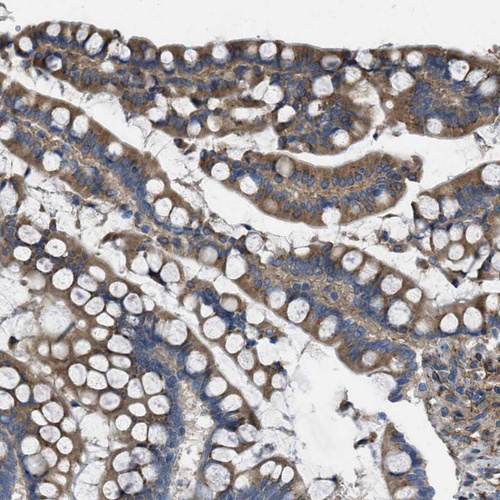

Immunohistochemical staining of human colon shows moderate cytoplasmic positivity in glandular cells.